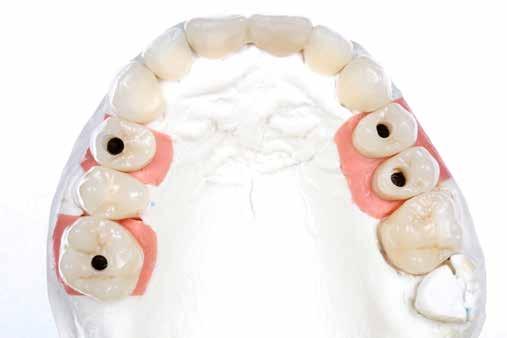

8. ábra. Az ultravékony héjak adhezív módszerekkel történő ragasztása. (A): Az elkészült héjak. (B): A fogfelszínek kofferdám izolálásban történő foszforsavas kondicionálása. (C): Az adhezív felvitele. (D): A héjak fényre kötő rezin alapú ragasztócementtel történő ragasztása.

ás, majd #0-ás retrakciós fonalakat (Ultrapak, Ultradent Products Inc, South Jordan, Utah, Egyesült Államok) helyeztünk. A végső precíziós lenyomatot polivinil-sziloxán lenyomatanyaggal (Virtual 380, Ivoclar Vivadent AG, Schaan, Liechtenstein) vettük. A fogtechnikai fázisban ultravékony (0,5 mm-nél vékonyabb) földpátkerámia héjak elkészítését kértük (Super Porcelain Ex-3, Kuraray Noritake Dental, Tokió, Japán), (7. ábra). A kerámia héjak készre vitelét követően a próba során a héjakat a helyükre illesztettük a széli zárást, az így kialakított fogformák ellenőrzése céljából. A páciens elégedett volt az így kapott látvánnyal. A végleges ragasztás kofferdám izolálásban történt. A preparált fogak felületét először 37%-os foszforsavval (Total Etch, Ivoclar Vivadent) 15 másodpercen keresztül kondicionáltuk, majd vízzel leöblítettük (8. ábra). A kondicionált zománcfelszíneket Adhese Universal (Ivoclar Vivadent) adhezívvel kezeltük. A kerámiahéjak homorú felszíneit 5%-os folysavval (IPS Ceramic Etching Gel, Ivoclar Vivadent) 20 másodpercen át kondicionáltuk, majd a felszíneket Monobond Plus primerrel (Ivoclar Vivadent) vontuk be (7. és 8. ábrák). A héjakat fényre kötő rezinalapú ragasztócement (Variolink Esthetic LC, Ivoclar Vivadent) applikálását követően a helyükre illesztettük. A kifolyó cementfelesleg eltávolítását követően minden felszínt (labiális, palatinális, meziális és distális) LED-es polimerizációs lámpával (VALO Cordless, Ultradent) 40 másodpercen keresztül megvilágítottuk.